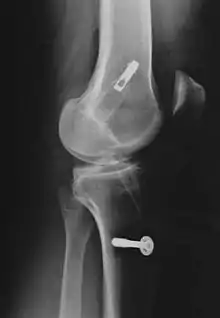

Pour la reconstruction du LC par transplantation autologue au moyen du tendon patellaire, une partie de celui-ci est prélevée avec des morceaux d'os aux extrémités, technique dite bone tendon bone (os tendon os), ou technique BTB. Il est tiré à travers des canaux élargis (8 à 10 mm de diamètre dans le tibia et le fémur). La longueur de chacun des blocs osseux est de 20 mm. L'ancrage le plus stable de la greffe est obtenu par fixation avec des vis d'interférence. Celui-ci est particulièrement important en vue d'une mobilisation fonctionnelle rapide.

Consolidation du transplant

Au début des années 1990, les transplants de tendons patellaires étaient fixés avec des vis d'interférence en titane soit aux deux bouts du transplant, soit uniquement au tibia, et fixés au fémur par un endobouton, enfilé sur le transplant. L'endobouton consiste en une bride de fil non résorbable munie d'une tête basculante en titane (plaque à quatre trous), que l'on bascule après un enfilage à travers le canal dans l'os[233]. Plus tard, on a utilisé des bioscrews (vis d'interférence résorbables) à la place des vis en titane[234], pour rendre une nouvelle opération d'enlèvement des vis inutile. Ces vis sont faites de polymères décomposables, comme un polylactide : Poly-L-lactide ou PLLA, ou poly-L-co-D/L-lactide ou PLDLLA. On peut aussi utiliser une technique hybride de vis résorbables (fixation intra-articulaire) et d'endobouton (fixation extra-articulaire). Dans la Press-Fit-Technik-Fixation, qui naît vers 1995, on peut complètement abandonner la fixation par les vis dans la technique BTB. Les extrémités osseuses sont usinées en cône, si bien qu'un bord-à-bord solide dans les canaux forés est possible. En 1996, on a utilisé des fraises commandées par robot pour faire ce joint, mais ce procédé n'a pu s'imposer en raison de son coût (en personnel et en appareils) et du manque de résultats indiscutablement meilleurs en opération.